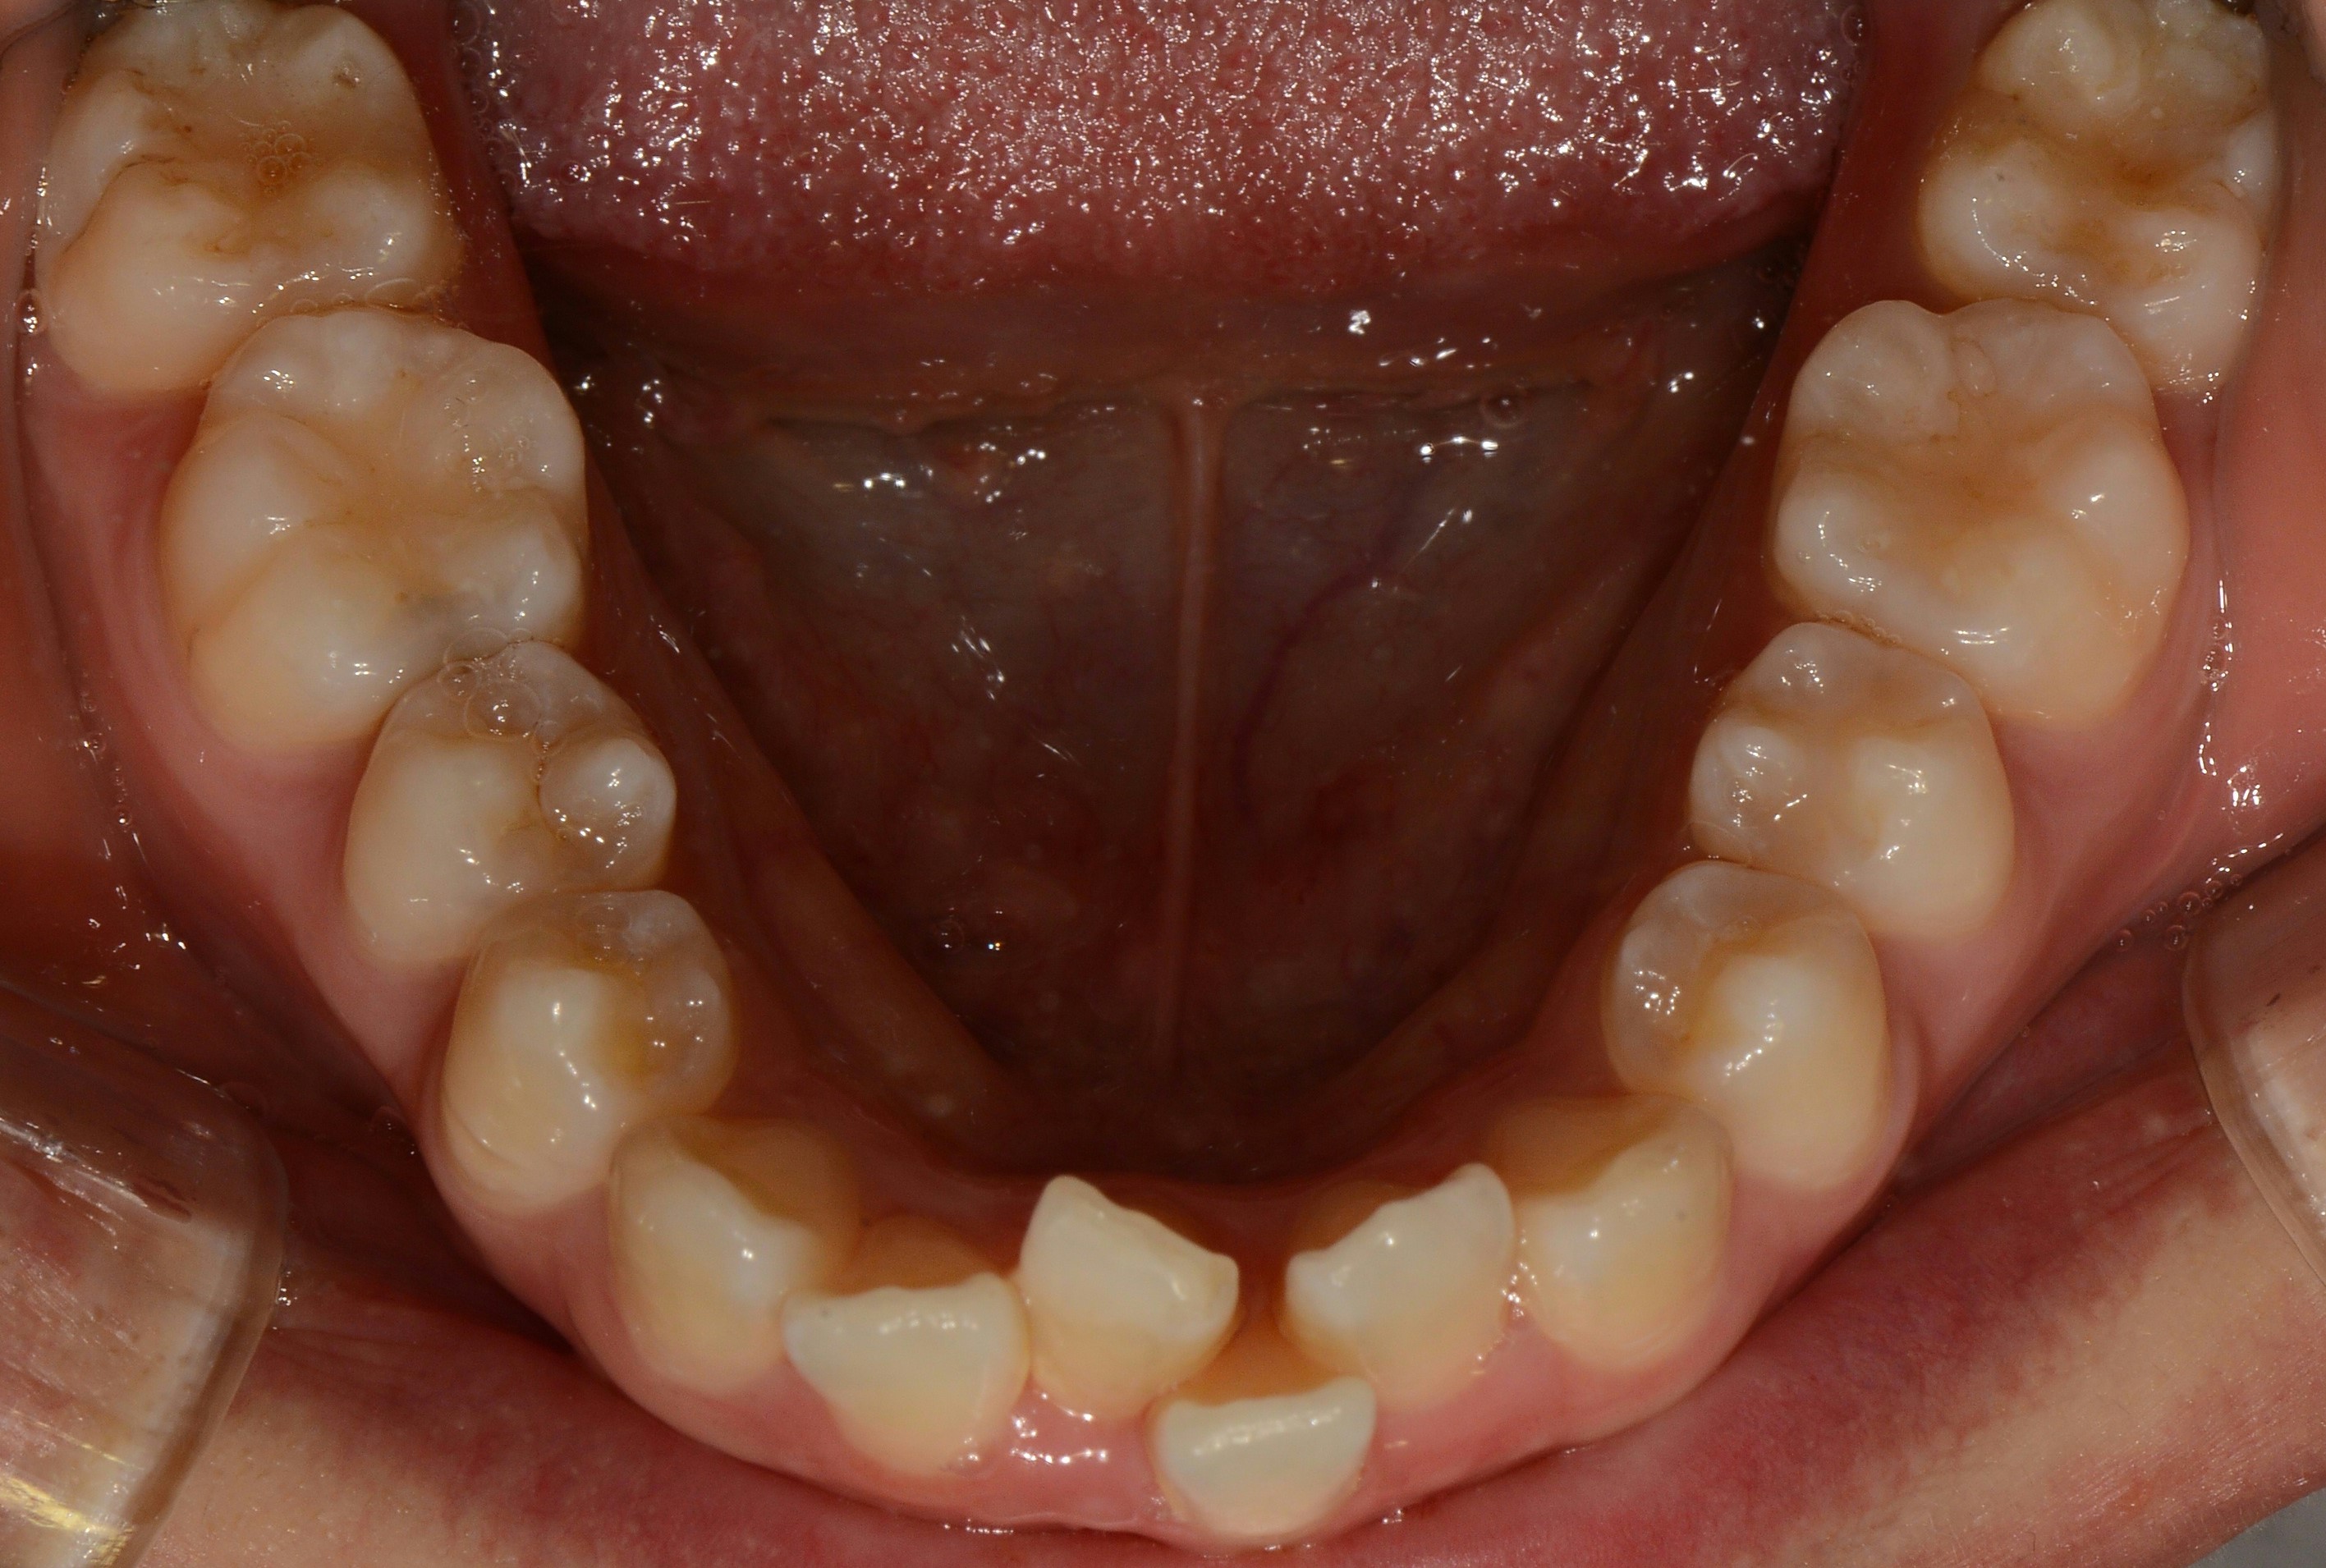

치료 전 사진입니다.